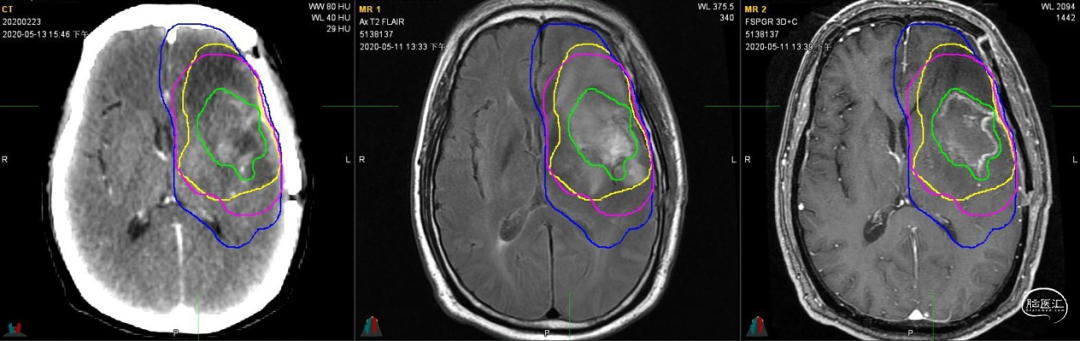

放疗靶区勾画:图示。

入院前头MRI(2020-3):左侧额岛叶肿块,信号不均匀,其内可见出血和坏死,占位效应明显,周围见水肿。考虑左额岛叶肿瘤(高级别脑胶质瘤可能性大)。于2020年4月行左额岛叶占位性病变切除术。术中见肿瘤组织位于左侧额中回及额下回后部,大小约4m×5cm×5cm,呈烂鱼肉样,色灰红,质软,部分坏死,血运中等,边界不清,侵犯左侧岛叶向下挤压颞叶。显微镜下沿肿瘤周边胶质增生带完整切除肿瘤。术后48小时内复查头MRI平扫、加强,影像显示术腔边缘不规则线样强化,靠近放射冠及侧脑室壁强化明显,可疑少许残存。

术后组织学诊断:高级别胶质瘤,WHO 4级;分子病理:IDH1 R132H野生型,1p19q 1p/19q未缺失,TERT C250T突变,BRAF V600E 无突变,MGMT启动子甲基化未检测到。整合诊断:胶质母细胞瘤(WHO 4级 IDH野生型)。